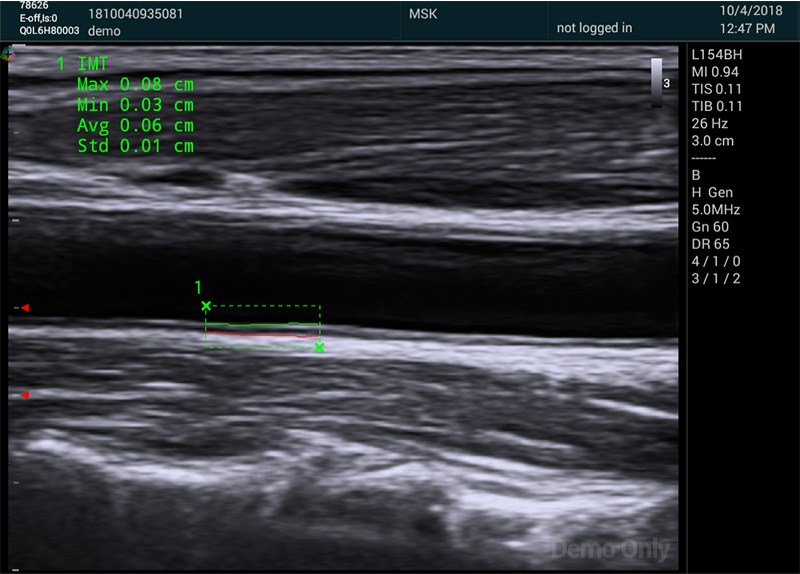

血管應用方面,自動IMT與手動測量相比提高了準確性,更快速更方便。系統(tǒng)可以自動描記并顯示結果。